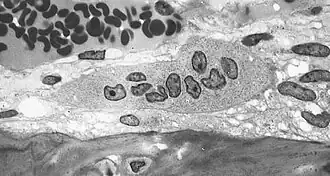

Резорбция костной ткани (разрушение, рассасывание кости, остеолиз) происходит при участии гигантских многоядерных клеток, так называемых остеокластов, которые также имеют большое количество лизосом, митохондрий и вакуолей.

Остеокласт — это основная клетка, участвующая в процессе резорбции кости. При активизации этих клеток у них появляется функциональная зона — «гофрированный край», или «щёточная каёмка». Гофрированный край представляет собой спирально-скрученную мембрану клетки с множественными цитоплазматическими складками, он обращён в сторону развивающегося процесса резорбции и является местом активного окисления тканей.[1]:26-28 Группа остеокластов растворяет минеральный компонент кости, а также гидролизует органический матрикс. Разрушение кости начинается с прикрепления остеокласта к минерализованной костной поверхности «гофрированным краем», через который выделяются гидролитические ферменты и протоны, а также различные интегрины (α₁, αᵥ, β₁, β₃), участвующие в растворении кости.[1]:28 Другие клетки, принимающие участие в резорбции костной ткани — это моноциты и макрофаги. Они взаимодействуют с костной тканью посредством фагоцитоза и хемотаксиса, в большинстве случаев действуя как «уборщики мусора». Помимо фагоцитарной активности продуцируются цитокины (ИЛ-1, ИЛ-1α, ИЛ-1β, ФНО-α и др.) влияющие на активизацию коллагеназ, разрушающих белковый матрикс. Кроме того, моноциты и макрофаги рассматриваются многими учёными как предшественники остеокластов.[1]:31-32 Имеются сведения о влиянии лимфоцитов на резорбцию костной ткани посредством секреции ФНО-β, а также через 1,25-дигидроксивитамин D и ПТГ, к которым лимфоциты имеют рецепторы.[1]:32